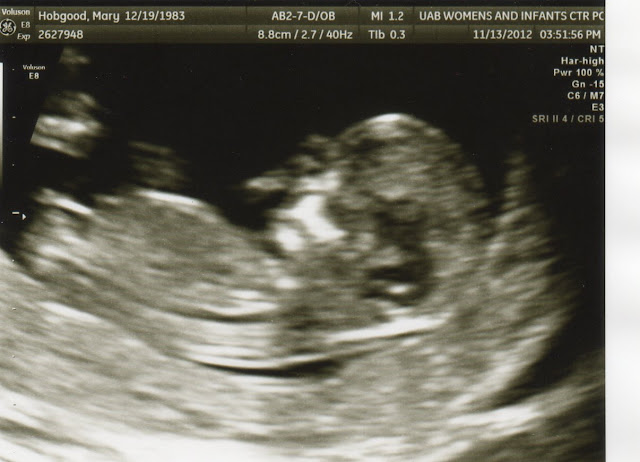

Yep, we are 13 weeks pregnant!! Here is our ultrasound at 12 weeks sleeping with his/her hand on its face.

Above is our ultrasound picture to ensure our baby was in my uterus-where it should be for the next 9 months. When we first found out we were finally pregnant, our doctors were not hopeful that this baby would live. They were concerned my hormones were not increasing like they should be and perhaps this baby was ectopic or I would miscarry. So we were in what I termed Pregnancy Purgatory. I knew I was pregnant, but my heart was guarded. It wasn't joyful like I imagined. We didn't get to surprise our parents with great news. We had to share with them that this may not be our time, but they were our prayer warriors. It was the most emotionally draining two weeks of my life waiting until we were far enough along to see on an ultrasound where our little one was. For those two weeks, I went to the doctor every other day for bloodwork.

Like I said earlier, our first ultrasound showed the baby was snug in my uterus, but we still had a long way to go. It wasn't until another week that we heard the baby's heartbeat. It was good and strong at 126 bpm, and the doctor told us it was a good sign of a healthy pregnancy. It was the most beautiful sound I had ever heard. I wish I had an ultrasound picture from that appointment, but I don't. Below was next week's ultrasound where the heart rate was 160 bpm.